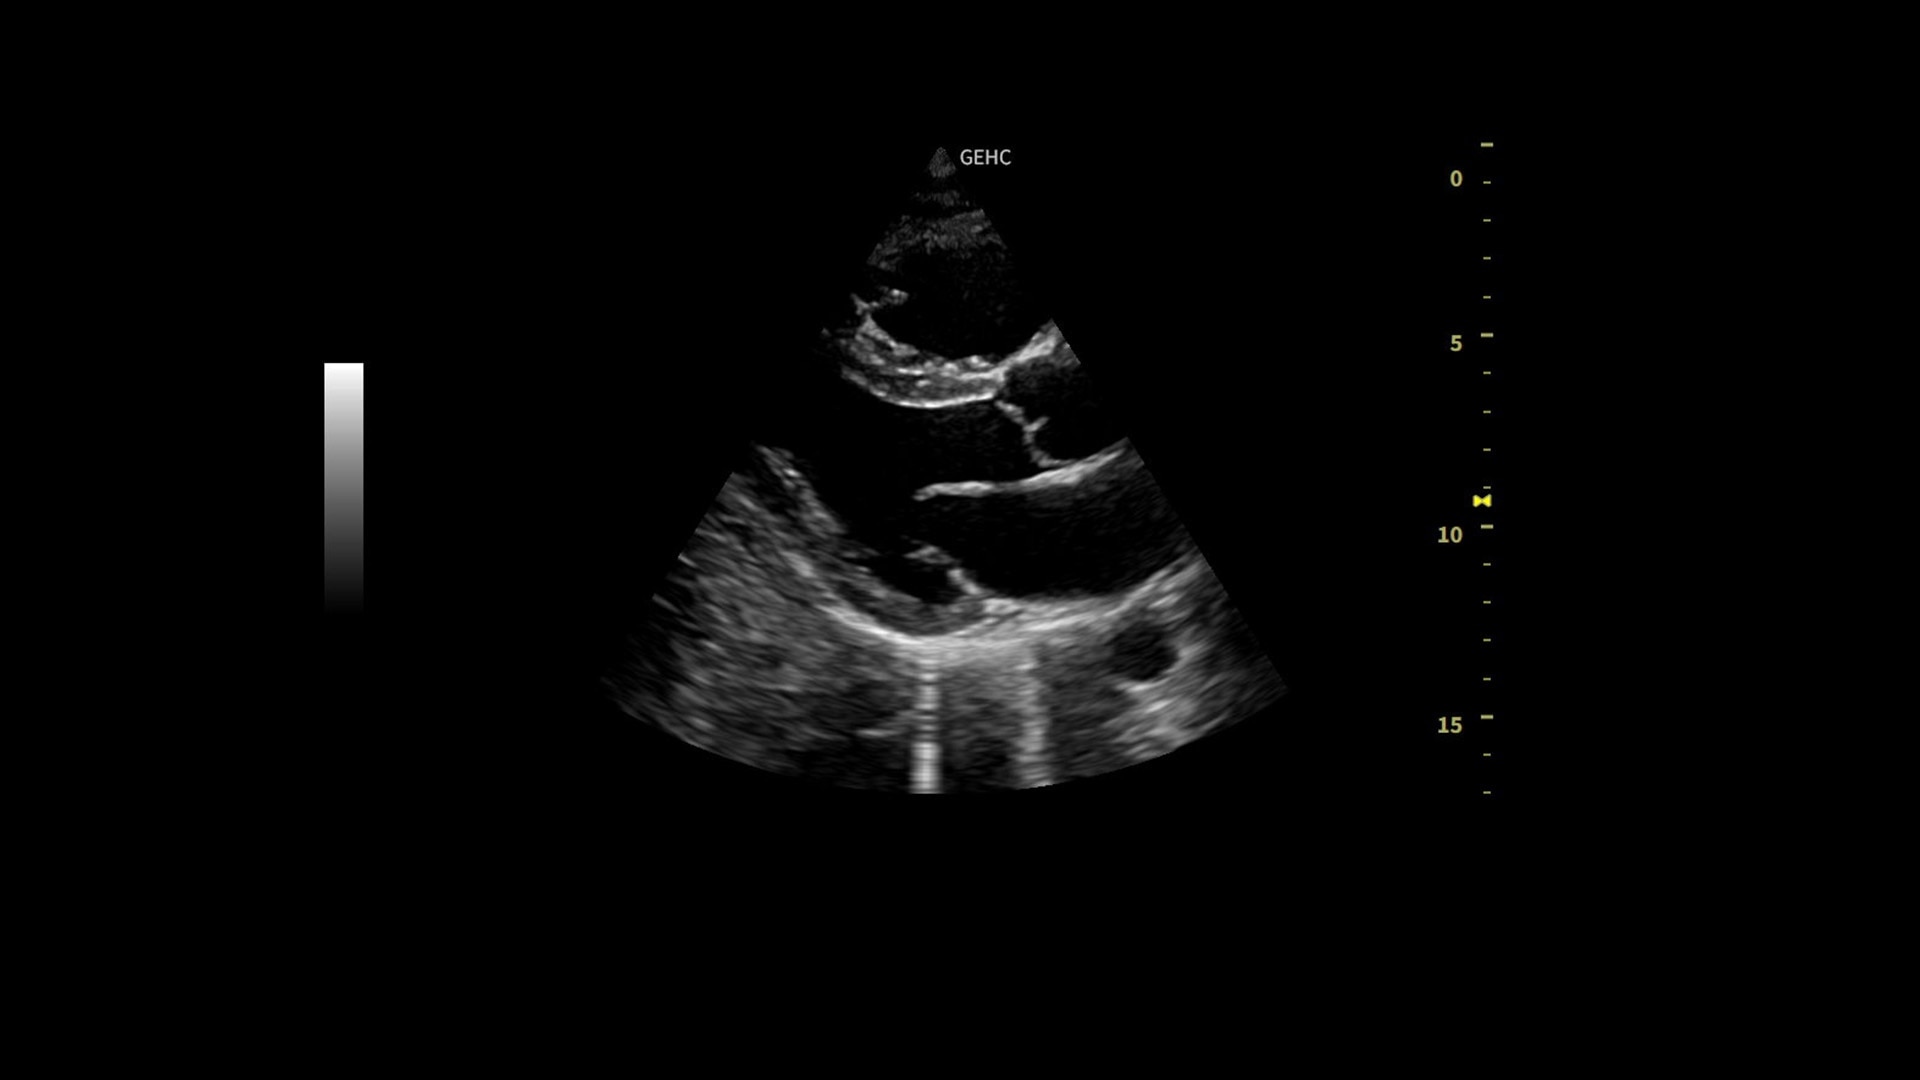

Clinical excellence

Easy to diagnose

Powered by VisionBoost Architecture, Versana Premier provides optimal image quality so users can easily reach a diagnosis. Advanced clinical features help address challenging cases while automated tools help reduce scan time:

• Optimize images while scanning with Whizz clinical features, easily improve Color Doppler with Whizz Color Flow, and view scans in the image style that suits your preference with Whizz Easy Style